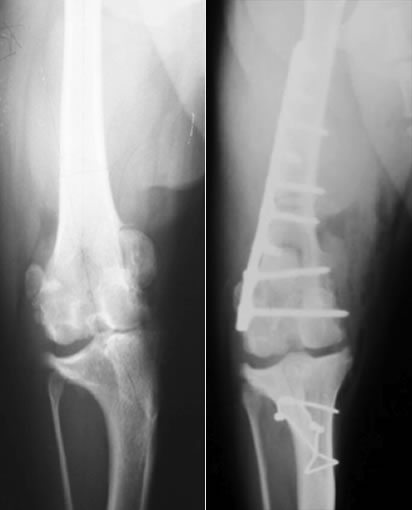

膝蓋骨脱臼グレード4とは

成長期に膝蓋骨が大腿骨遠位にある滑車溝から脱臼し、大腿骨や脛骨の変形が急速に進行し、膝蓋骨が脱臼し固定されている状態。指で脱臼をなおそうとしても戻らない状態。

触診、レントゲン検査

外科手術が適応であれば、Block Resectionによる造溝術と脛骨粗面転移術に加え、必要に応じて変形した大腿骨を矯正する骨切り術を同時におこない、膝蓋骨が正しい位置におさまるようアライメントをただします。